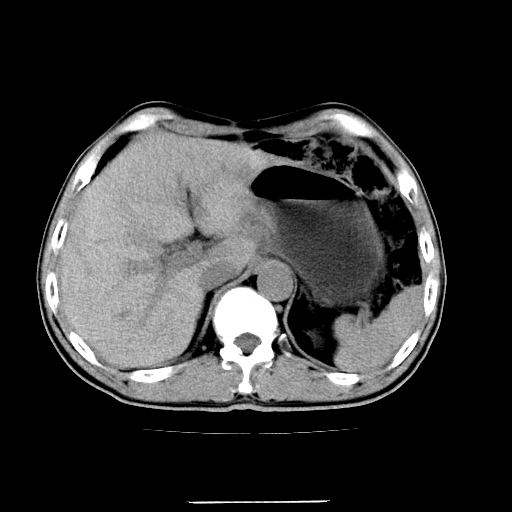

增强第6幅图上有气液平相通,是肠管,右肾低密度灶形态不规则似有壁结节,不除外转移.

应该考虑是肠管,理由1、平扫和增强对比,形态和内部的密度有明显改变。2、增强图片可见明显气液平面。

是肠管影。还有右侧肾盂旁囊肿。

另外,胰腺体部密度在平扫和增强时均不太均匀,似有数个小的囊状低密度区存在。不知道增强时其他期如何?应该高度警惕为转移性病变。

胰头右侧低密度影卡考虑为肠管;胰头前部低密度影,增强环形强化,结合临床首先考虑转移灶,其次考虑淋巴结结核(中心干酪性坏死)。

如是转移灶强化多为均质强化。如是结核应见到完整的壁且壁略厚。如是转移虽壁可不完整但内壁应该不规则。所以不支持是结核或转移。敬请指正!

是肠管影。还有右侧肾盂旁囊肿